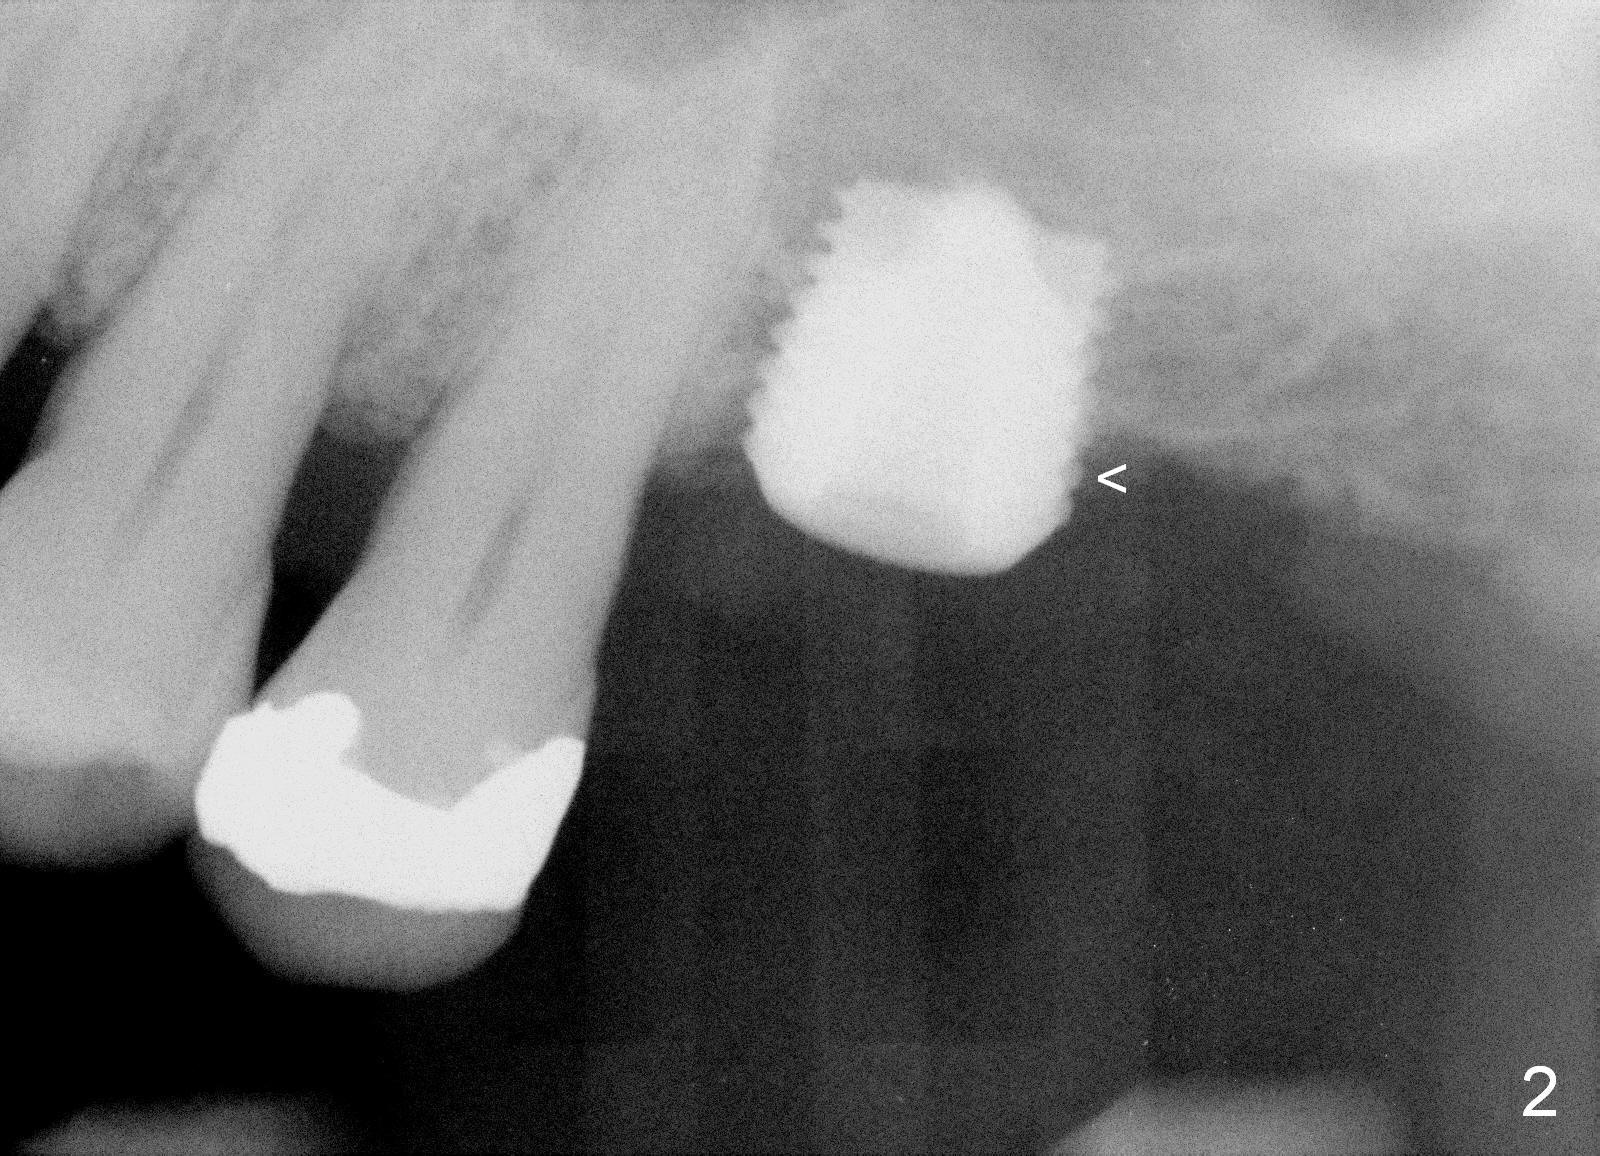

The implant recipient site is wide buccopalatally. After incision, a 3.9/4.7 mm trephine bur (from UF Extra Wide Implant kit) is used to initiate osteotomy 2.5 mm from the distal surface of the tooth #13. The depth of the trephine bur is 2 mm. The block of bone is difficult to be removed from the osteotomy. It is pushed into the sinus with a 3.5 mm osteotome with minor membrane perforation. The perforation is getting worse when allograft and Osteogen is being pushed upward. It is repaired with insertion of Osteotape and more durable collagen membrane, followed by bone graft. The osteotomy opening is enlarged slightly with a 6x6 mm tapered drill, followed by insertion of a 6.5 mm tap. When a 7x6 mm bone-level implant is placed with >60 Ncm, the axis is not parallel to that of the neighboring teeth. The implant is backed up and re-directed. The trajectory is changed within normal limit (Fig.2); the torque is slightly less than before. The distal 2nd thread is outside the crestal bone (Fig.2 <). The implant is placed deeper so that the distal 2nd thread is almost subcrestal (Fig.3). The remaining threads are covered by bone graft, followed by collagen membrane. There is tension to close the wound. A cemented abutment is placed (6.8x4(2) mm) to hold perio dressing in place. Postop instruction is given, including sinus precaution. Afrin is prescribed. The patient continues using Amoxicillin and Chlorhexidine postop. Surprisingly, there is no sinus symptom postop. The perio dressing remains in place 1 week postop (Fig.4). Later on, mild infection develops around the implant orally. One week of Amoxicillin is prescribed. The symptom improves. One month postop, the patient returns for follow up: the distal implant plateau is exposed (Fig.5 I). A provisional is fabricated for protection of the wound and comfort (Fig.6 P). The exposed plateau should be able to be covered by the gingiva in a few months.